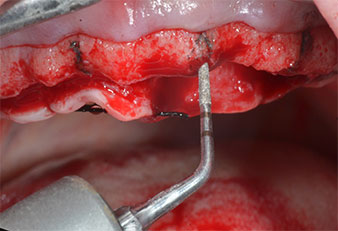

Ein flammenförmiges, diamantiertes piezochirurgisches Instrument (Piezomed I1) wurde verwendet, um die Implantatpositionen zu markieren und die Pilotpräparationen durchzuführen (Abb. 3). Dabei wurde darauf geachtet, eine Auf- und Abbewegung mit reduzierter Leistung, voller Spülung und niedrigem Druck (unter 300 g) anzuwenden. Als Nächstes wurde ein Pilotinstrument (Piezomed I2A/I2P) zur initialen Erweiterung der Implantatlager auf einen Durchmesser von 2 mm verwendet (Abb. 4), gefolgt von einem 3-mm-Instrument (Abb. 5).